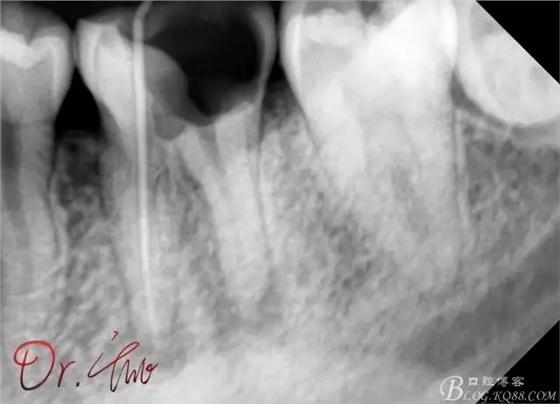

初診照

拍片確定長度

第一次試主尖

第二次試主尖

根充